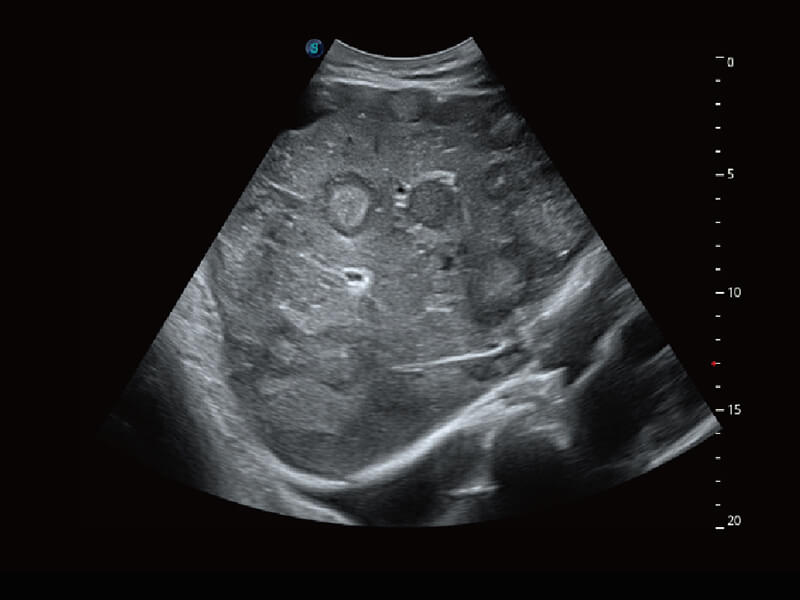

超宽频带技术,为容积成像带来优质的二维图像基础,为您呈现丰富的结构细节,栩栩如生地展示宝宝的宫内形态以及各种组织的立体结构。